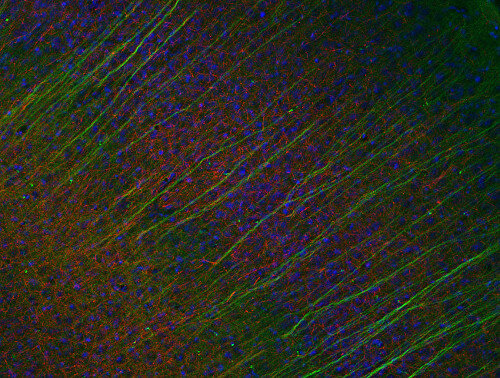

ICC: 1 : 500 gallery

IHC: 1 : 500 gallery

IHC-P: 1 : 500 gallery

Immunocytochemistry (ICC) on 4% PFA fixed cells. Immunoreactivity is usually revealed by fluorescence. Some antibodies require special fixation methods. For details, please refer to the “Remarks” section.

Immunohistochemistry (IHC) on 4% PFA perfusion fixed tissue with 24h PFA post fixation. Immunoreactivity is usually revealed by fluorescence or a chromogenic substrate. Some antibodies require special fixation methods or antigen retrieval steps. For details, please refer to the ”Remarks” section.

Neurofilaments (NFs) are intermediate filaments essential for providing structural support to neurons, particularly within axons. They play a crucial role in maintaining axonal diameter, which directly influences nerve conduction velocity (1). Neurofilaments are composed of three primary subunits - NF-L (light), NF-M (medium) and NF-H (heavy) – along with an NF-associated protein. In the adult central nervous system (CNS), α-internexin serves as the fourth neurofilament subunit, whereas in the peripheral nervous system (PNS), peripherin takes on this role (2).

Beyond their structural function, neurofilaments are also valuable biomarkers in both research and clinical settings. They are widely used in immunohistochemistry to stain and visualize axons, particularly in peripheral nerves and the CNS. Increased levels of neurofilament proteins in cerebrospinal fluid (CSF) or blood are strongly associated with neurodegenerative diseases, such as amyotrophic lateral sclerosis (ALS), multiple sclerosis (MS), and Alzheimer’s disease (3). In peripheral nerve studies, neurofilament staining is often combined with other markers, such as S100, to provide a more comprehensive assessment of nerve structure and pathology (4).